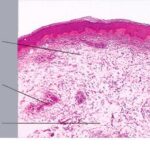

Histopathology.

The epidermis and papillary dermis are usually normal. Mucin in large amounts is present in the dermis,

particularly in the upper half . As a result, the dermis is greatly thickened. The mucin occurs not only as individual threads and granules but also as extensive deposits resulting in the splitting up of collagen bundles into fibers and wide separation of the fibers. As a result of shrinkage of the mucin during the process of fixation and dehydration, there are empty spaces within the mucin deposits. The number of fibroblasts is not increased as a rule, but in areas where there is much mucin, some fibroblasts have a stellate shape and are then referred to as mucoblasts . A perivascular infiltrate of lymphocytes may be seen in some cases, and mast cells are moderately increased in number .